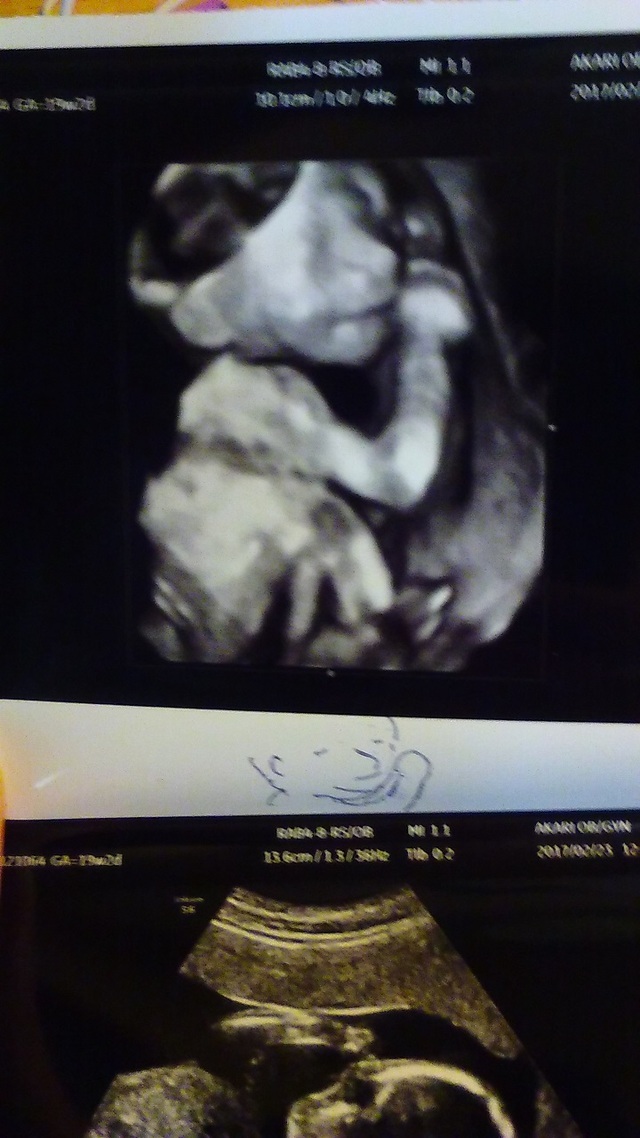

19週3日(19w3d・女の子)|すけろく さん(32歳)

エコー写真撮影時のエピソード:

だいぶお腹が大きくなってきて、服によっては妊婦さんとわかるようになってきた頃です。ムカムカしたり、日によって食べれるものが違ったり、食べ過ぎたりしていたつわりも少し収まって普通の食事ができるようになってきた頃で体調は落ち着いていました。お父さんはいつも検診に行っていましたが、いつも顔を見せてくれて嬉しそうでした!この頃から骨がしっかりしてきて肋骨が立派に見えるのがこの写真のお気に入りポイントです。

このしばらく後に転居し、4Dエコーをやってくれない病院になってしまったので顔がはっきり見られなくなって残念です。